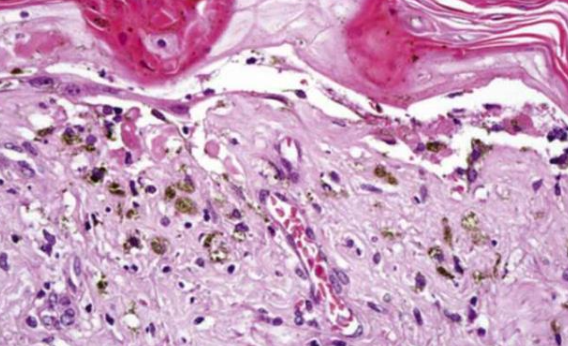

Incontinentia Pigmenti

(色素失調病,Bloch-Sulzberger syndrome )

X顯性

GENE: NEMO (NFκB Essential Modulator)

剛出生

• 先天免疫 gg

• CNS (30%)

• 眼睛 (35%): 斜視(strabismus)、眼球震顫(nystagmus)、白內障(cataracts)、視網膜血管異常、視神經萎縮

• 皮膚: 水皰期 → 疣狀期 → 色素過度沉積階段 → 萎縮和脫色階段

• 口腔: 同 EDA mutation

水皰期

上皮內裂解,內部充滿嗜酸性球

疣狀期

過度角化, acanthosis, papillomatosis

色素過度沉積階段

皮下結締組織 melanin-containing macrophage,即黑色素失調(melanin incontinence) alt text